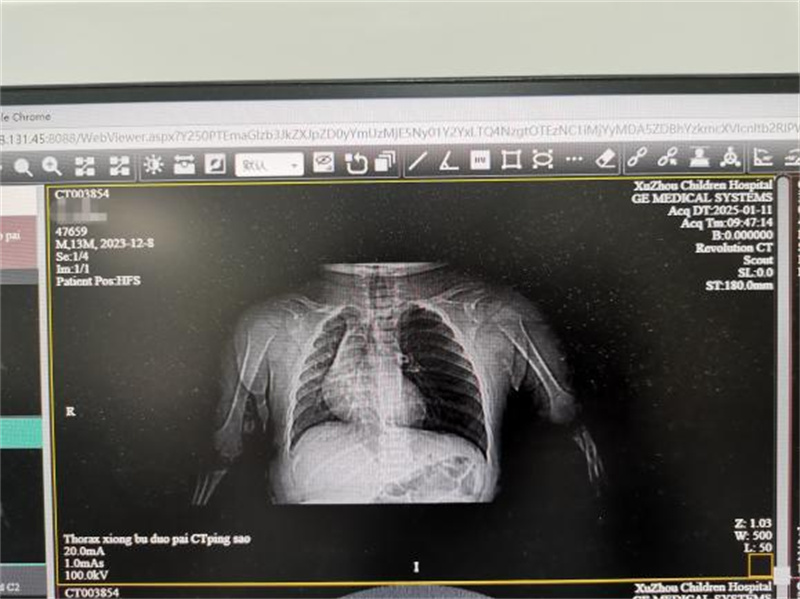

幸运的是,经过两三天的治疗,小宝宝的病情明显好转,体温正常了,咳嗽和气喘也减轻了,呼吸也平稳了。现在,心电监护和吸氧都可以撤掉了,小宝宝终于可以去做影像学检查了。因为小宝宝有反复咳嗽、气喘的病史,这次病情又来势汹汹,还合并了甲型流感病毒感染,陈医生决定给他做胸部CT检查。

检查结果一出来,放射科就急急忙忙地打电话来报危急值。原来,CT报告显示小宝宝的左侧支气管里可能有异物。异物在呼吸内科并不罕见,小孩子吃东西时容易呛到,有时候家长喂食瓜子、花生时,孩子一呛咳,东西就可能掉进支气管里。支气管里的异物会引起反复咳嗽、喘气,甚至堵塞气道,引起肺不张,划破气道黏膜还会咯血、甚至支气管穿孔。在临床上,支气管异物属于危急情况,需要立即报告。